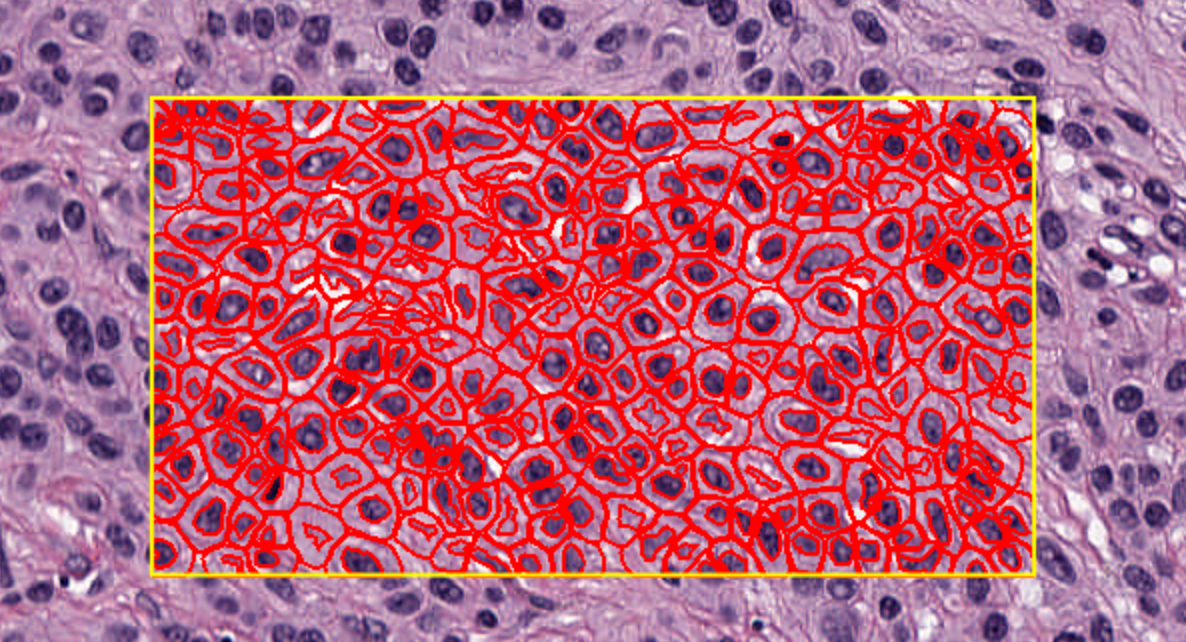

接下来,尝试在注释内部创建检测对象。首先,在图像中包含细胞的区域绘制一个注释——最好是相当小的区域,包含大约100个细胞。

点击对话框底部的“运行”按钮。几秒钟后,您所选区域中的细胞应该会出现。这些细胞是您的第一个检测对象。

2-10:显示与隐藏

随着图像上对象数量的增加,可能会变得杂乱或令人困惑。有四个有用的工具栏按钮可以帮助自定义对象如何显示。

这些按钮允许您快速切换显示标记,以在查看分析数据和底层图像之间切换。

您还可以在图像上右键点击,进一步修改细胞显示的方式,即是否显示核或边界。